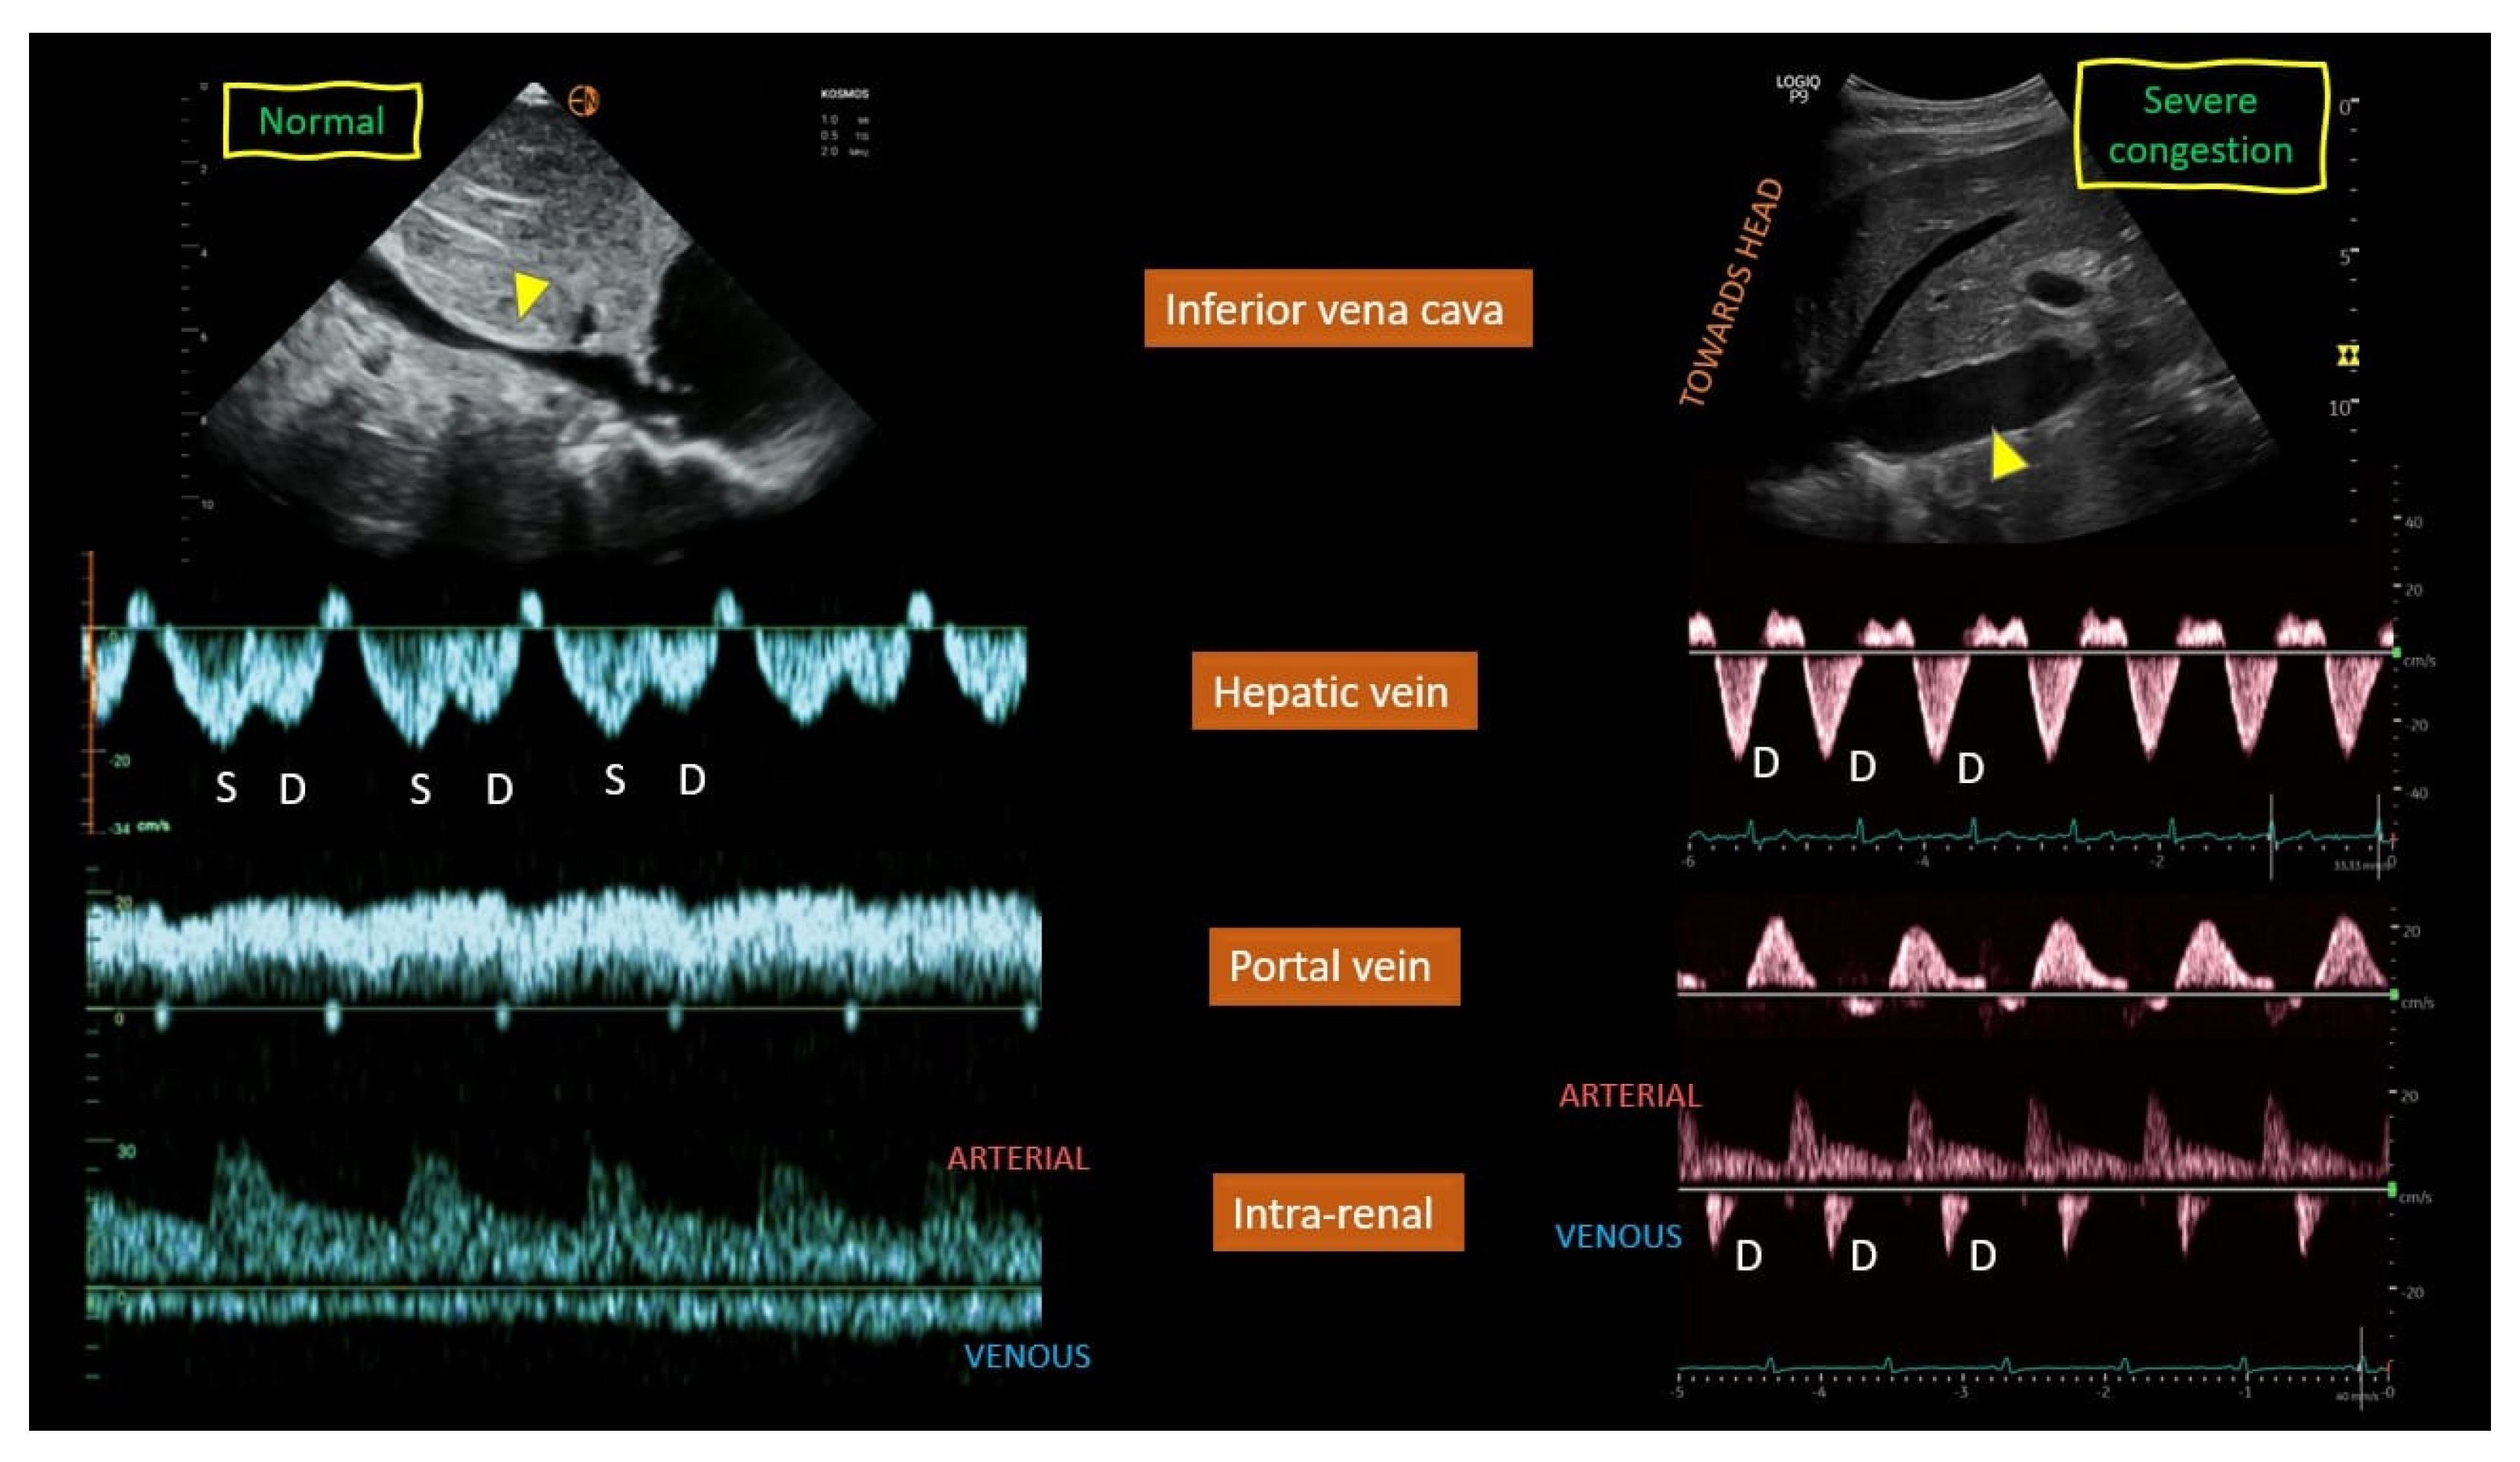

- Hepatic Vein Doppler: In normal conditions, hepatic vein (HV) flow is pulsatile, corresponding to the RAP waveform. Pathologies like right ventricular dysfunction or tricuspid regurgitation can alter HV waveforms, and increasing RAP can reduce venous return during systole, leading to distinct changes in the waveform.

- Portal Vein Doppler: Normal portal vein flow is continuous, but severe venous congestion can cause pulsatility in the portal circulation. The pulsatility fraction (PVPF: [(Vmax − Vmin)/Vmax] × 100) quantifies this, with values above 30% indicating mild abnormalities and above 50% suggesting severe congestion [57]. Elevated PVPF is a strong predictor of acute kidney injury in post-cardiac surgery patients.

- Intra-Renal Vein Doppler: Similar to the portal vein, intra-renal veins show continuous flow under normal conditions, but congestion leads to a pulsatile pattern. This can manifest as a biphasic pattern in moderate congestion and a monophasic pattern in severe cases [114]. Altered intra-renal flow is associated with poor outcomes in heart failure and pulmonary hypertension patients [56,114].

- Grading Venous Congestion: Venous congestion is categorized into grades 0–3 based on waveform alterations, a system known as VExUS (Venous Excess Ultrasound Score) (Figure 14) [63]. This grading system provides a practical method for assessing the severity of venous congestion in clinical settings (Figure 15).